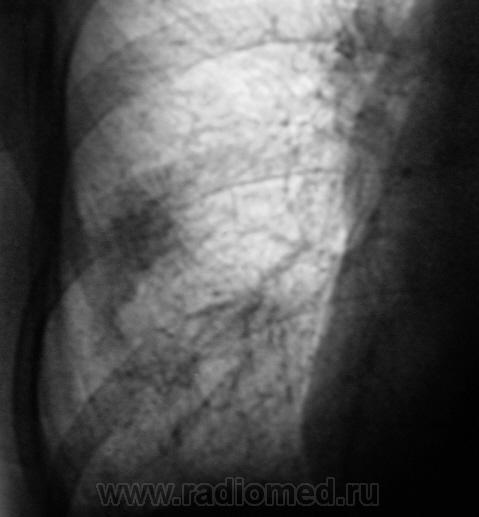

Флюорограмма - 2010 г.